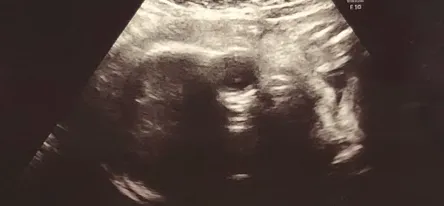

妊娠初期からのエコーと同様に赤ちゃんの発育状態に異常がないかを確認します。

推定体重や頭のサイズ、大腿骨の長さなどを測ります。

8ヶ月になるとお顔もはっきり見えるようになり、4Dでは表情もよく見えます。

そのはずですが・・・我が家の赤ちゃんは手をクロスにしてお顔を隠していたので、一切見ることができませんでした。

- 頭の横幅・・・7.38cm

- 大腿骨の長さ・・・5.2cm

- 推定体重・・・1350g

赤ちゃんの平均体重はこの時期(29週)1050g〜1550gと言われていますので、平均でした。

頭は下を向いているので、正常位置でした。